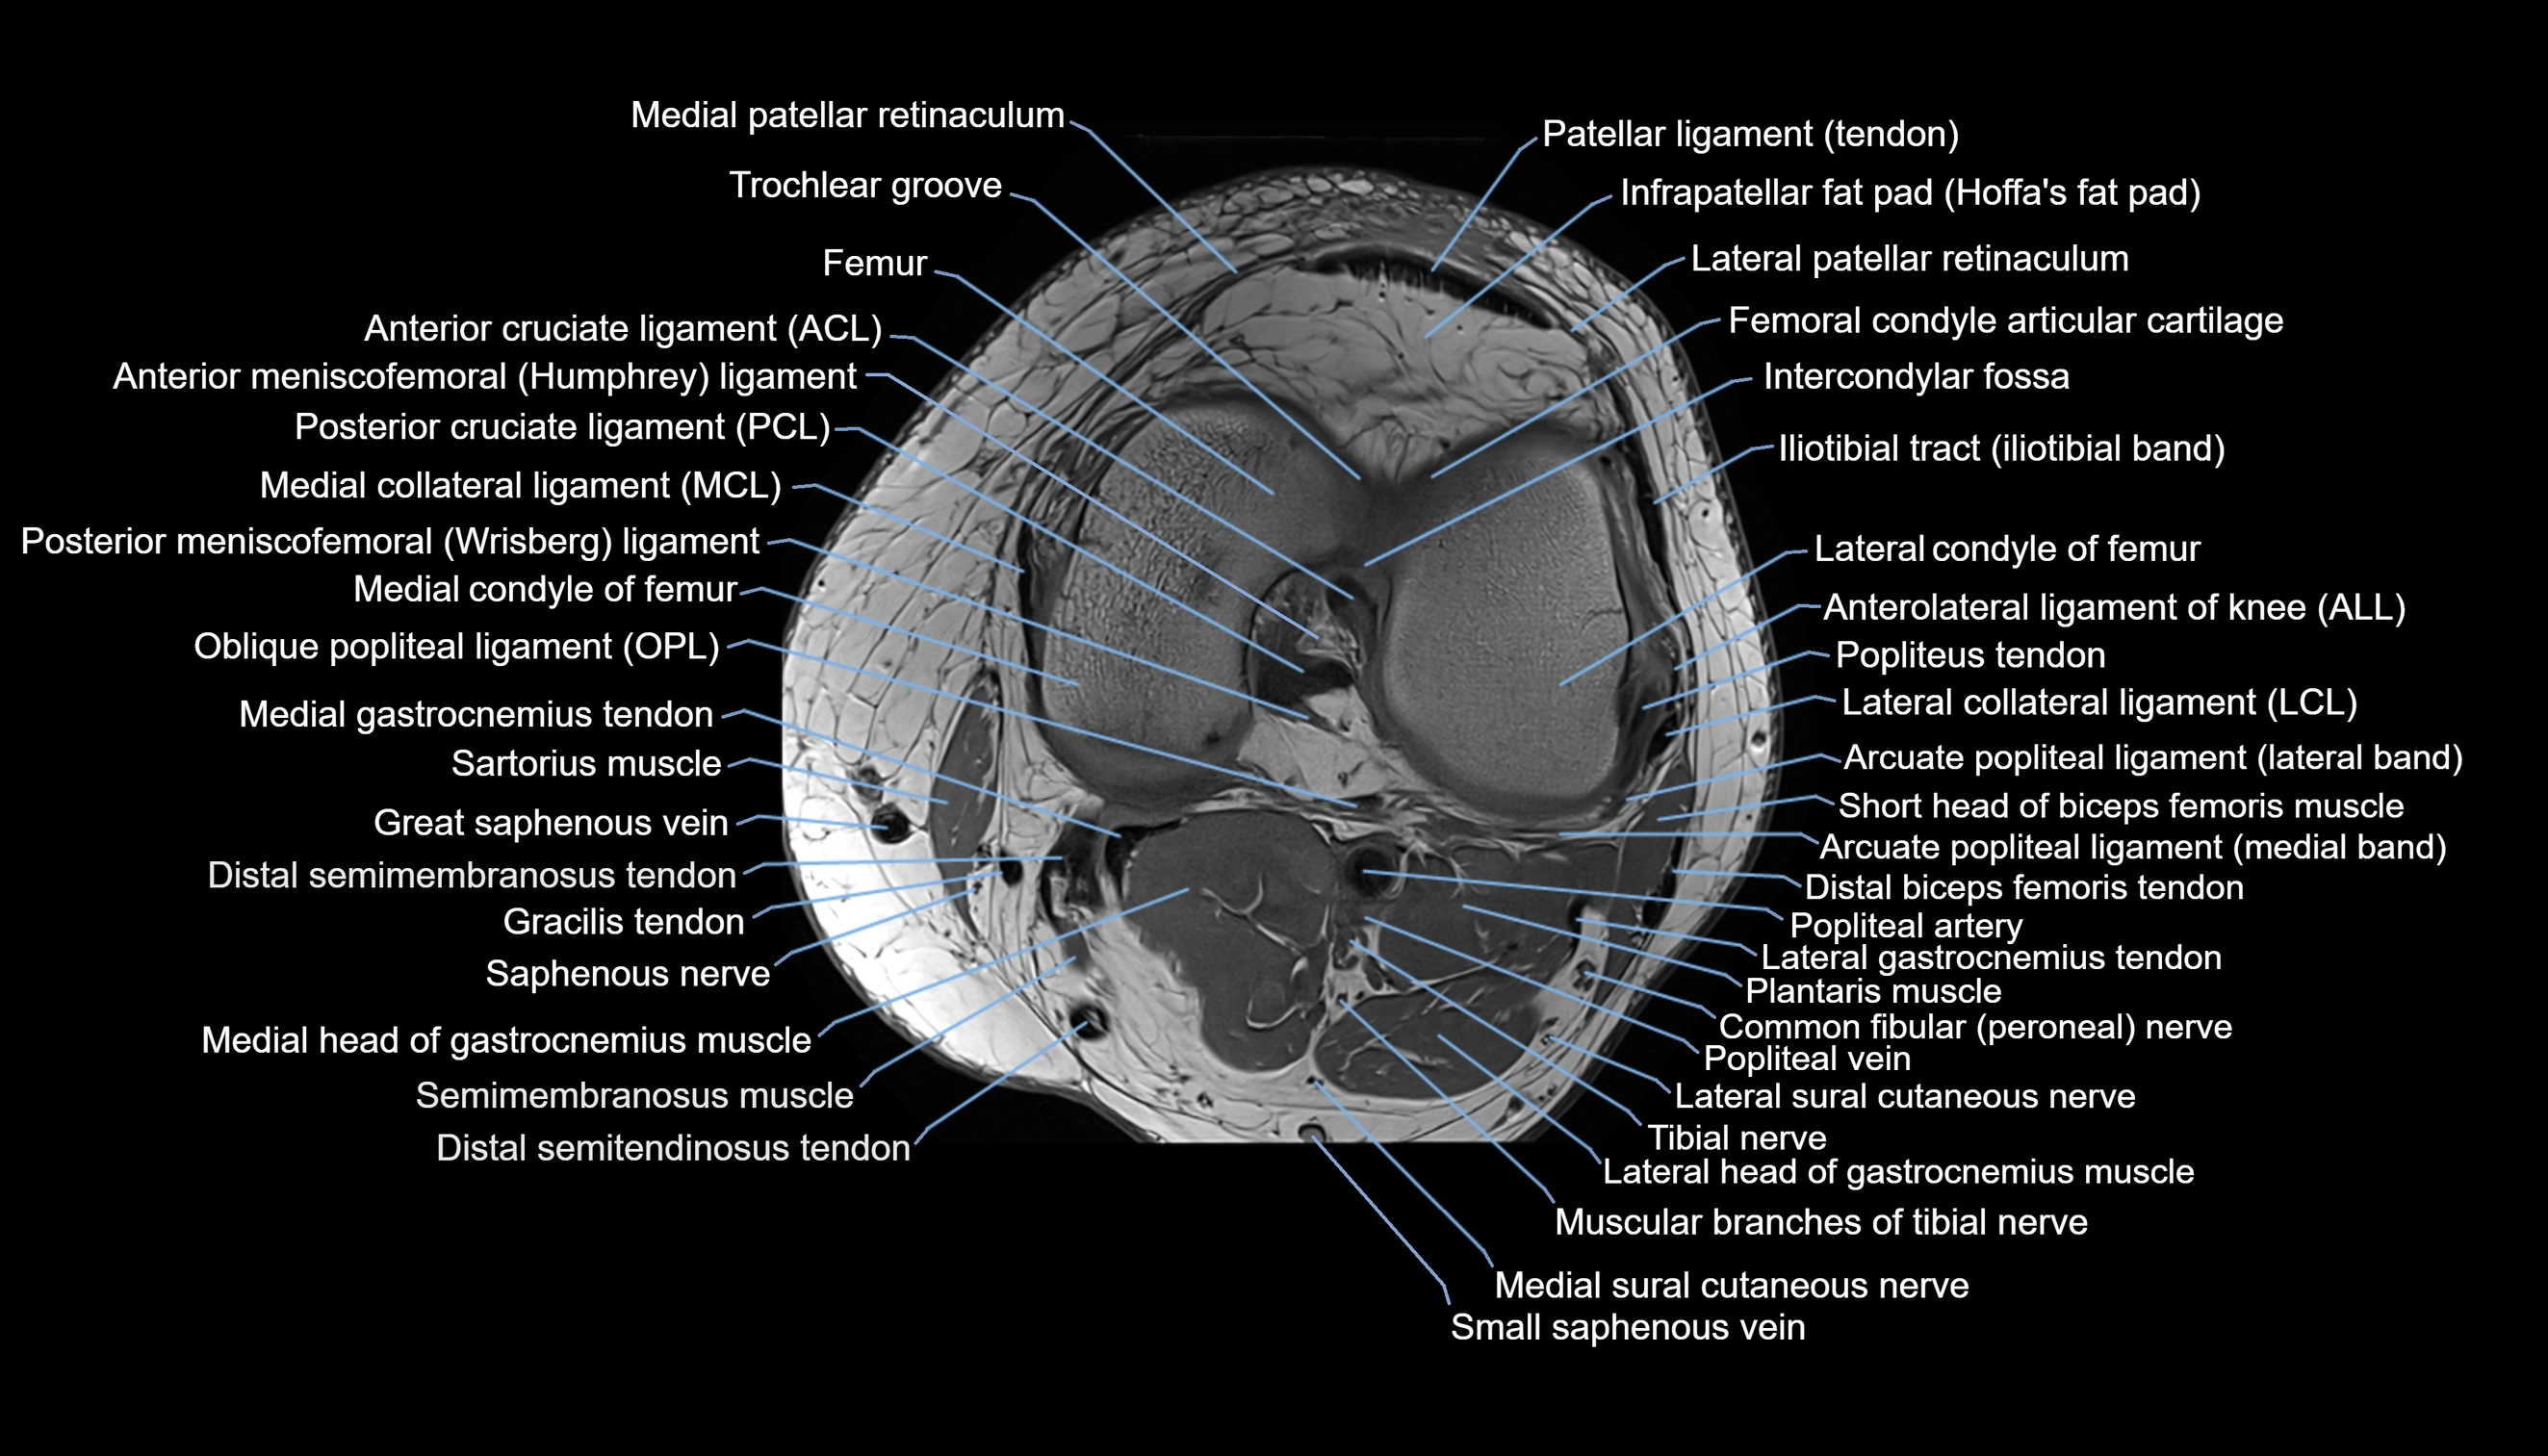

- Anterior cruciate ligament

- Anterolateral ligament of knee

- Arcuate popliteal ligament

- Femoral condyle articular cartilage

- Gastrocnemius muscle

- Intercondylar fossa

- Lateral collateral ligament

- Lateral condyle of femur

- Lateral gastrocnemius tendon

- Lateral head of gastrocnemius muscle

- Lateral patellar retinaculum

- Lateral sural cutaneous nerve

- Medial collateral ligament

- Medial condyle of femur

- Medial gastrocnemius tendon

- Medial head of gastrocnemius muscle

- Medial patellar retinaculum

- Medial sural cutaneous nerve

- Muscular branches of tibial nerve

- Oblique popliteal ligament

- Patellar tendon (patellar ligament)

- Popliteal artery

- Popliteal vein

- Popliteus muscle

- Popliteus tendon

- Posterior cruciate ligament

- Posterior meniscofemoral ligament

- Saphenous nerve

- Sartorius muscle

- Sartorius tendon (Distal)

- Small saphenous vein

- Soleus muscle

- Tibial nerve

- Trochlear groove

- great saphenous vein

- Anterior meniscofemoral ligament